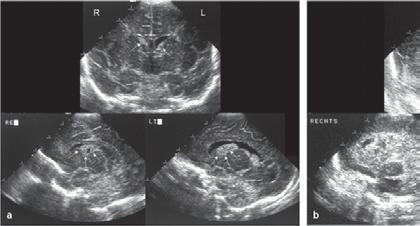

1.6.5 Krvácení do mozku (intrakraniální krvácení)

n Definice

Krvácení do mozku je častou komplikací u nedonošených novorozenců, které může vést ke vzniku hydrocefalu a k dlouhodobým neurologickým postižením.

n Epidemiologie